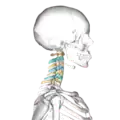

Position of cervical vertebrae (shown in red). Animation. -

Shape of cervical vertebrae (shown in blue and yellow). Animation. -

Cervical vertebrae, lateral view (shown in blue and yellow) -